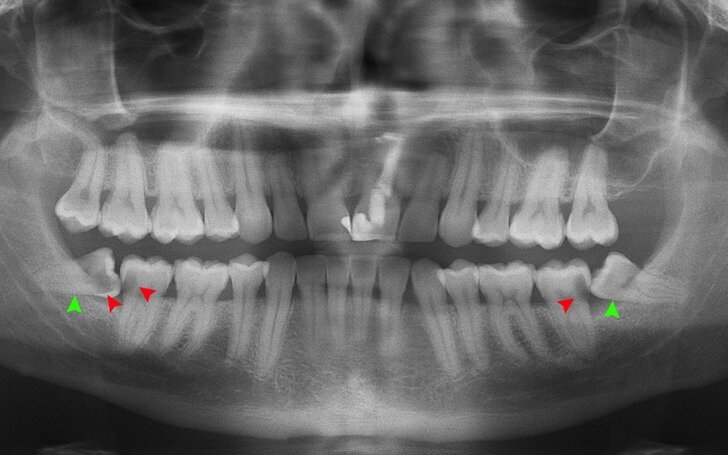

9. Приблизительно от 5% до 37% людей не имеют зубов мудрости с рождения. Эти зубы, скорее всего, не появятся, потому что они больше не нужны. Наши предки нуждались в них, чтобы жевать грубую и твердую пищу, такую как коренья, листья, орехи и мясо.